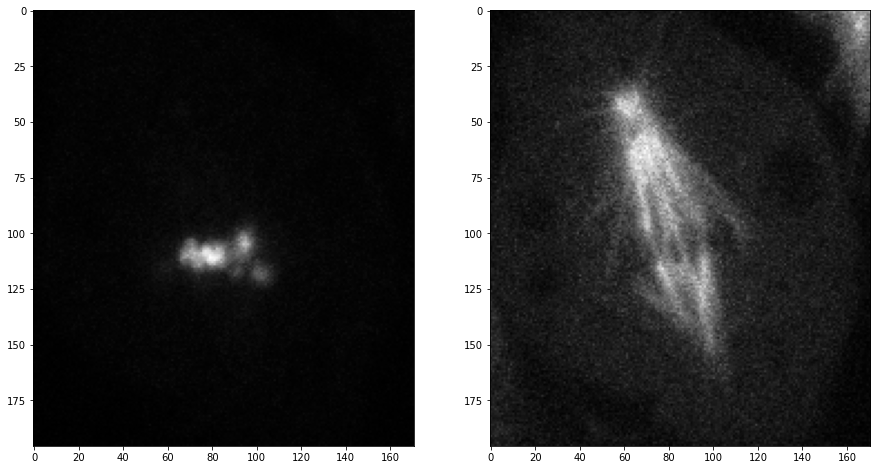

Comme les trois dimensions sont des dimensions spatiales, nous pouvons également faire des coupes orthogonales au plan de l’image et correspondant aux plans anatomiques. Pour orienter correctement les images, nous pouvons transposer leurs axes en ajoutant .T à la fin.

saggital = image_stack[:,:,128].T

coronal = image_stack[:,128,:].T

transverse = image_stack[96]

fig, axs = plt.subplots(1, 3, figsize=(15,15))

# afficher les plans orthogonaux

axs[0].imshow(saggital, cmap='Greys_r')

axs[0].set_title('Sagittal')

axs[1].imshow(coronal, cmap='Greys_r')

axs[1].set_title('Coronal')

axs[2].imshow(transverse, cmap='Greys_r')

axs[2].set_title('Transverse');